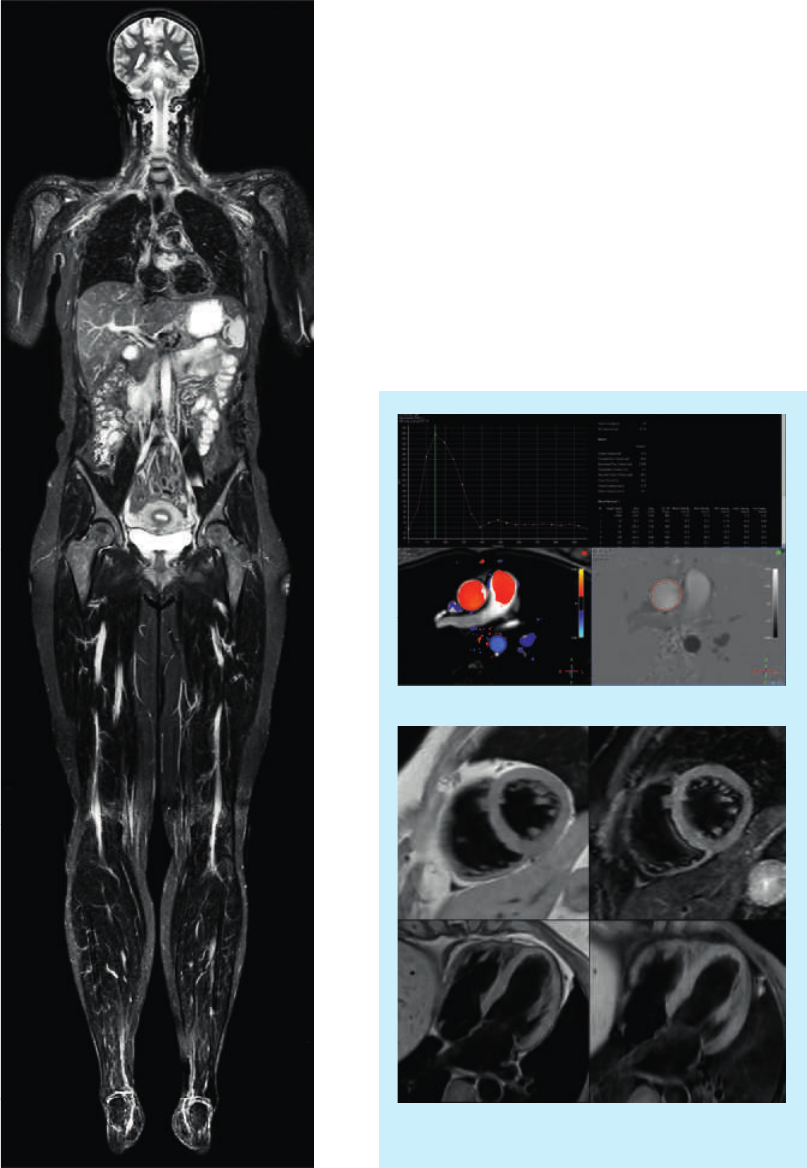

New solutions for emerging applications

In addition to the growth in traditional applications of MR, there is an increasing role for MR in

oncology and cardiology applications. Designed to address these trends, Ingenia 1.5T provides

advanced functionality for oncology and cardiac applications, safeguarding your investment.

Differentiate your practice with oncology imaging

As MR continues to demonstrate value in cancer

imaging, staging, treatment planning and monitoring,

offering oncology services is of growing interest.

The Ingenia 1.5T positions your practice to provide

outstanding oncology services.

Ingenia 1.5T advantages:

•The accuracy provided by the magnet’s high

homogeneity, combined with the exceptional linearity

of the gradient coil, makes it ideally suited to address

diagnostics through therapy planning.

•Fusion of anatomical and diffusion data delivers robust

and sensitive results in a timeframe comparable to

the gold standard PET-CT exam, bringing whole

body oncology staging and follow-up to the clinical

mainstream.

•The ultra-large FOV with 70 cm bore can facilitate

imaging in the treatment position for possible future

radiation therapy applications.

•FlexTrak Mammo, a dockable patient support and on-

console breast biopsy planning system, allows seamless

integration of breast MR into your department.

3D T2W VISTA Breast

High quality multi-station body DWI

Cardiac imaging made easy

Ingenia 1.5T with dStream and Elite Cardiac Clinical

Solutions advances cardiac MR workflow to mainstream

use.

•Powerful clinical tools such as kT-BLAST, PSIR, and

volumetric imaging for cutting edge, one-stop cardiac

MR exams.

•Supporting dStream coil solution and wireless VCG for

high quality cardiac imaging.

•Workflow support tools such as Real Time interactive

planning and Cardiac Explorer for task-guided

processing including automated segmentation, screen

layout and reporting.

Quantitative flow analysis of the aorta

Black Blood cardiac imaging with and without fat

suppression

Fast whole body

T2W imaging